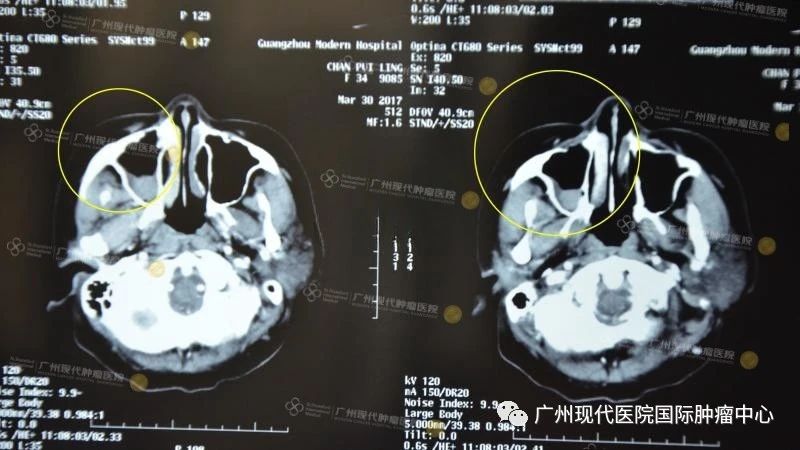

(2017年2月治疗前)

(鼻窦腔内被瘤物质充满,眼球被挤压移位)

(2017年3月,第一次介入治疗后)

(鼻窦腔内瘤物质减少,空腔基本恢复正常,眼球恢复正常)

(治疗前VS第一次治疗后)